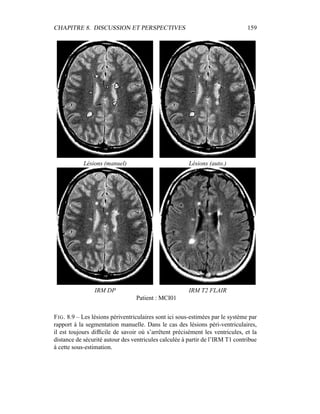

si les 4 séquences (T2 FSE / DP, T1, T2 FLAIR) sont disponibles, la segmenta-

tion ne sera menée dans un premier temps que sur le couple T2/DP, alors que les

autres séquences – T1, T2 FLAIR – montreront tout leur intérêt pour la détection

des lésions et leur spécification : ceci permet de n’effectuer la segmentation que

sur des images vierges de tout rééchantillonnage. En outre, nous ferons délibéré-